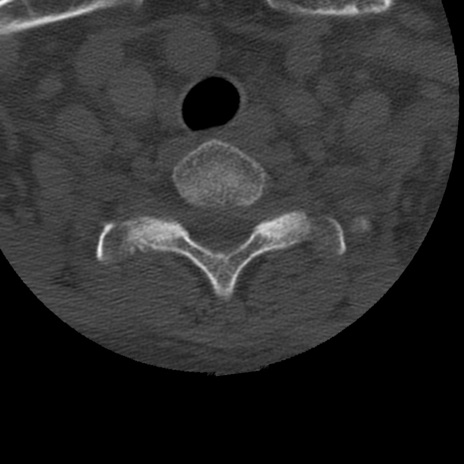

症例50 頚椎CT(横断像)

頚椎CT